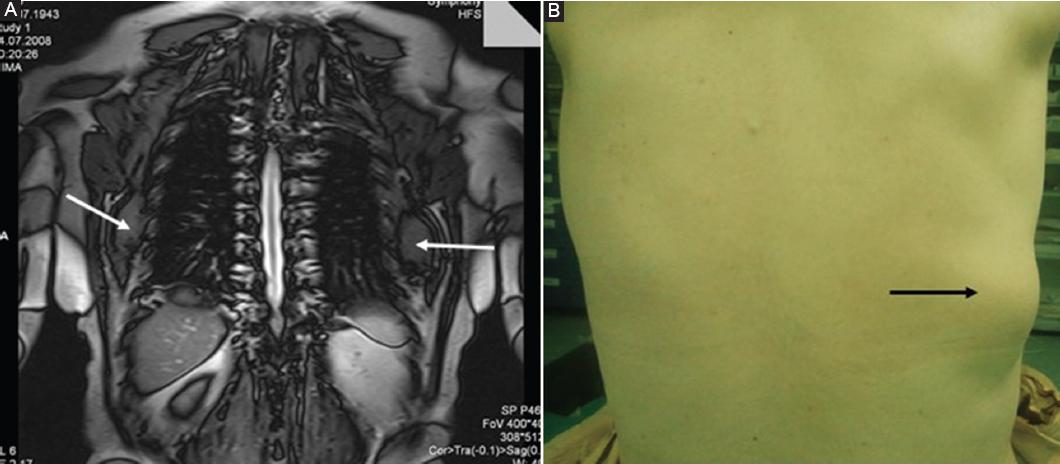

Patients with signs of swelling in the subscapular region underwent a physical examination followed by a magnetic resonance image (MRI) to evaluate the tumors position and its relationship with surrounding tissue (Fig. 1A and B). No diagnostic biopsies were performed before surgery. Any post-operative recurrences or other anomalies were evaluated using ultrasonography.

Figure 1 A: T1-weighted coronal magnetic resonance image of ED in a case with bilateral involvement (white arrows). B: view of ED in the lower corner of the scapula (clearly visual with anterior flexion of arm black arrow).

Sixteen of the study patients (80%) were female, and 4 (20%) were male. Swelling and back pain were the main complaints in 80% of patients, and a visual mass was observed in all patients in the subscapular region during anterior flexion of the arm (Fig. 1B). Limited shoulder mobility was observed in twelve patients (30%), and four (20%) were asymptomatic. An opening snap was observed in two patients (10%). The mean age was 61 years (with an overall age range of 41-74). Bilateral tumors were present in ten patients (50%), and unilateral lesions were more common on the right side (60%) (Table 1). Excisional surgery was performed on all patients, and tumors were completely removed (Figs. 2A and B).

The diagnosis of ED is usually based on clinical examination and radiological imaging. The mass can be more easily palpated when the arm is flexed anteriorly13,14. MRI is the preferred imaging modality as it can accurately determine the size of the tumor, its borders, and its relationship with the surrounding tissue8,15. In a typical ED MRI, the interposed areas of decreased signal intensity also appear as low signal intensity on T2-weighted sequences16.